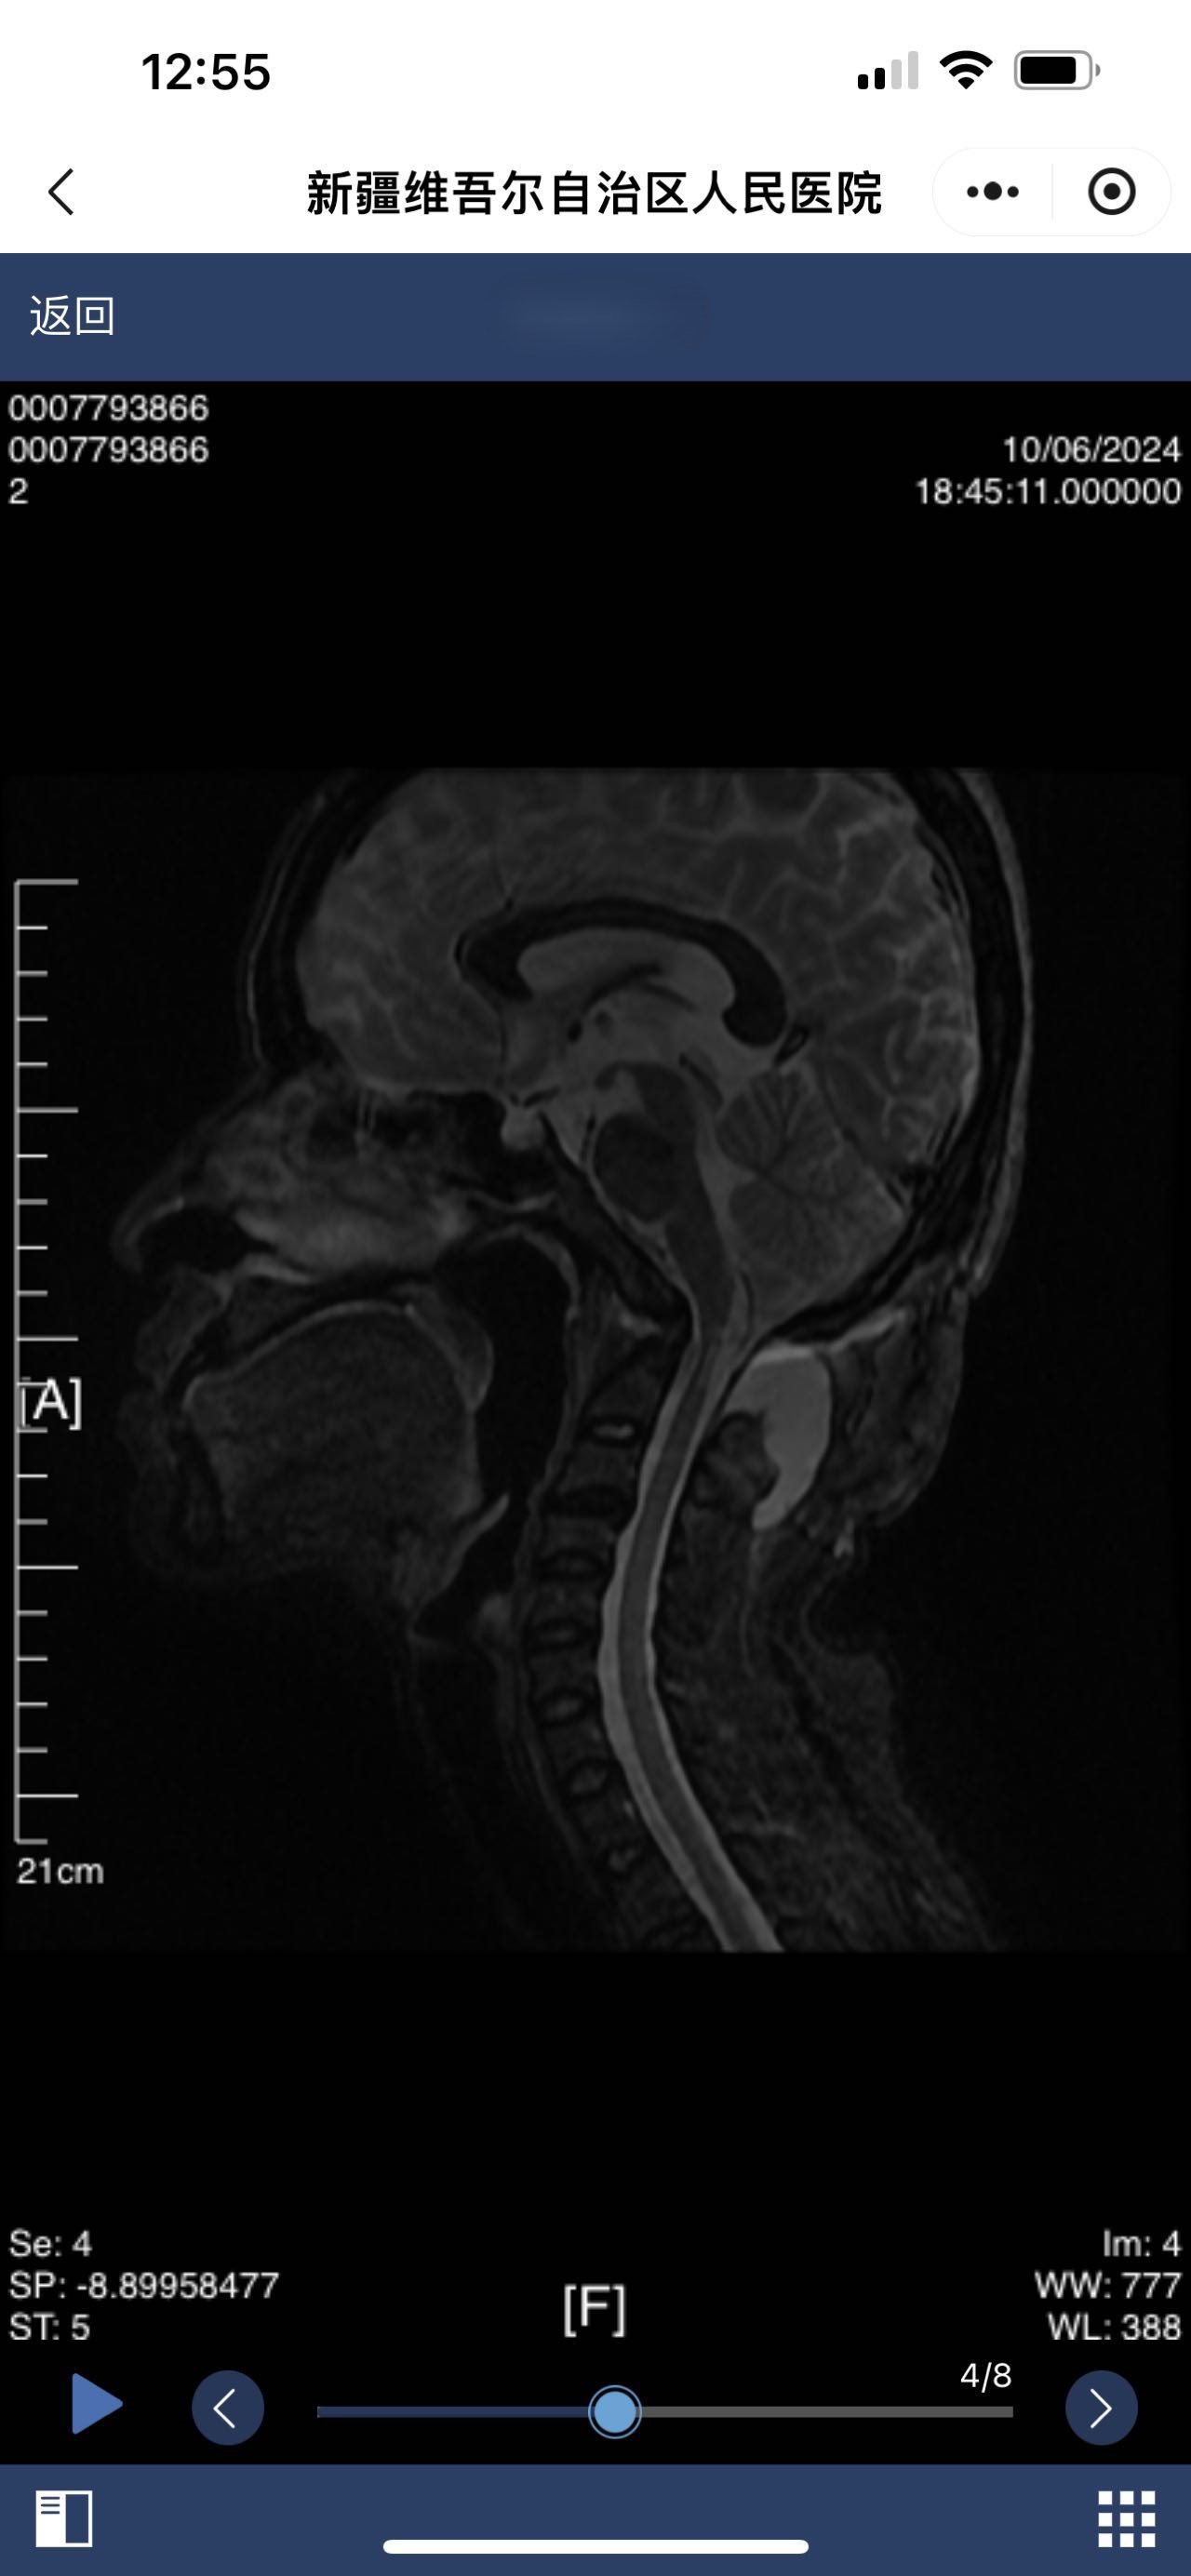

• 术后影像:

• 2024.10.06,积液范围略小。